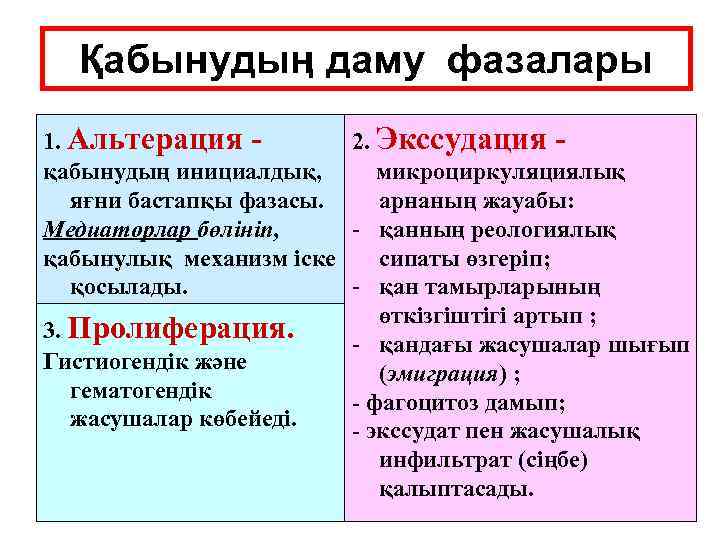

Қабынудың даму фазалары 1. Альтерация 2. Экссудация қабынудың инициалдық, микроциркуляциялық яғни бастапқы фазасы. арнаның жауабы: Медиаторлар бөлініп, - қанның реологиялық қабынулық механизм іске сипаты өзгеріп; қосылады. - қан тамырларының өткізгіштігі артып ; 3. Пролиферация. - қандағы жасушалар шығып Гистиогендік және (эмиграция) ; гематогендік - фагоцитоз дамып; жасушалар көбейеді. - экссудат пен жасушалық инфильтрат (сіңбе) қалыптасады.